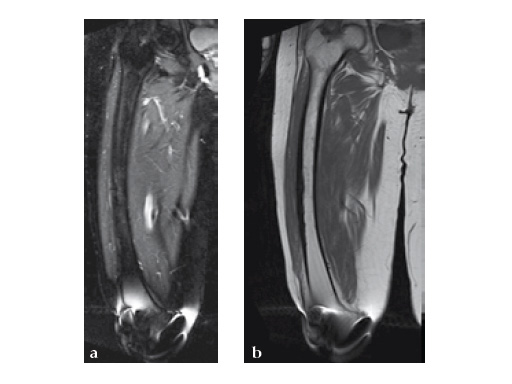

Insertion of A2FN as patient may be suffering from a stress fracture related to long term (2.5 years) bisphosphonate use. My rationale against a plate is because bisphosphonate related fractures will heal extremely slowly. In our experience even despite bone grafting union may need up to 2 years. In that time, a plate will fail in less than a year even if the patient is only allowed very minimal weight bearing.

Note despite the increased in curvature compared to other nails in the market, there is still noticeable malreduction at the fracture site (see Fig 6a-b).